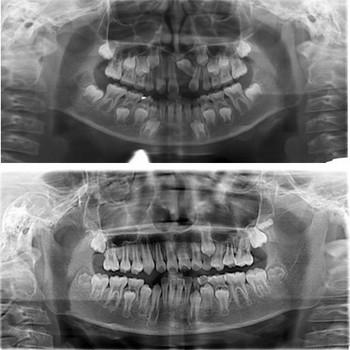

矫治前后全景片对照:

功能矫治前后全景片对照: